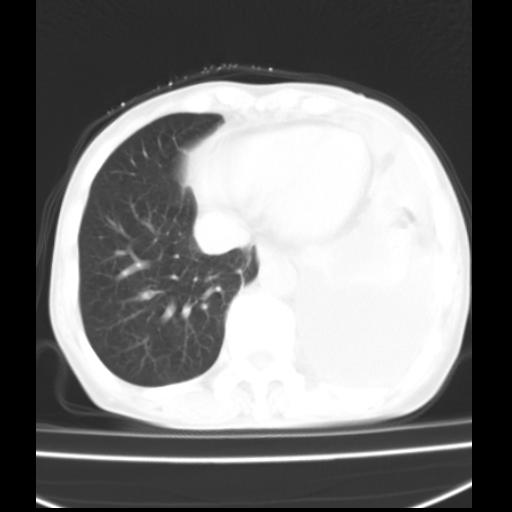

以下是引用随光逐影在2010-3-24 19:15:00的发言:[br]结合病史,考虑双肺及纵隔淋巴结多发转移、左侧胸膜转移并左侧大量胸水,左下肺膨胀不全。

以下是引用zxl51642在2010-3-24 18:49:00的发言:[br]结合乳腺癌术后病史,考虑双肺及纵隔淋巴结多发转移、左侧胸膜转移并左侧大量胸水、左下肺膨胀不全。